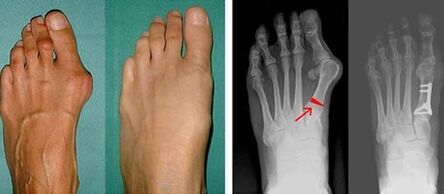

Pirmajā lielā pirksta un mazā pirksta valgus noteikšanas posmā ārsts veic vizuālu pārbaudi. Tādā veidā tas nosaka patoloģijas attīstības stadiju. Lai noteiktu detalizētas izmaiņas locītavās, tiek noteikti rentgena stari un plantogrāfija.

Ja vizuālā pārbaude un rentgens nedod nekādu rezultātu, tad pacients tiek nosūtīts uz plantogrāfiju, lai noteiktu iespējamo plakano pēdu. Šī metode ietver pēdu nospiedumu noņemšanu, uz kuru pamata pacientam izgatavo apavus vai zolītes ar ortopēdiskām īpašībām. Pēc tam pacientam tiek nozīmēta podometrija. Šī metode izmanto datora analīzi, lai noteiktu cilvēka svara spiedienu uz kājām. Uzlabotās diagnostikas rezultāti ir pamats pirmā un otrā pirksta izliekuma ārstēšanas metodes izvēlei.